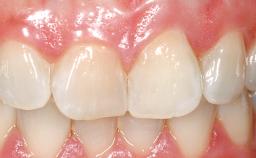

Immediate Placement of an Implant in a Maxillary Left Central Incisor Site

A 33-year-old female patient presented with an upper left central incisor that required extraction after a failed endodontic therapy. The tooth had been traumatized when the patient was a teenager and had undergone several endodontic treatments, including two apicectomy procedures. The patient was in good health and did not smoke. Clinical examination showed that the patient had a high lip line. In full smile, the gingival margins of the upper teeth were visible to the first molars. The gingival margins of central incisors 11 and 21 were only just showing. Examination of tooth 21 confirmed that the tooth was mobile and had hypererupted by 1 mm.